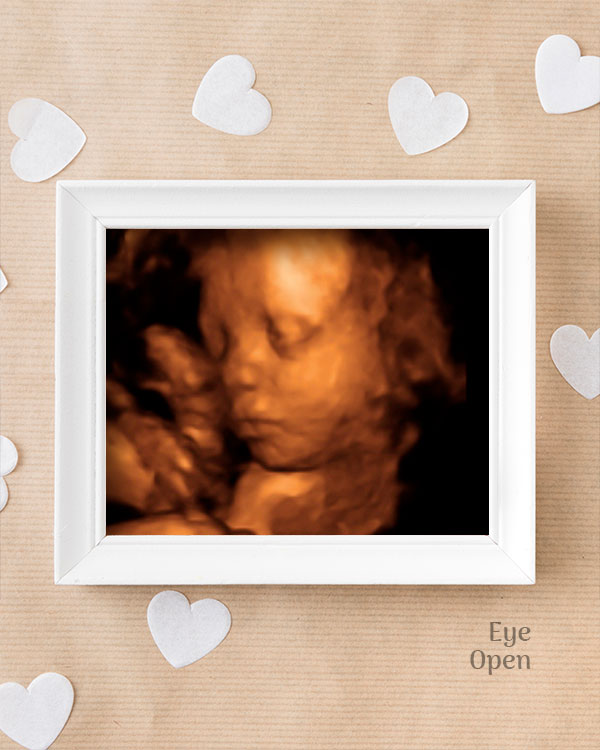

3D / 4D Baby Scan

Mediserv Diagnostics pioneered 4D scanning in the Malabar region. These advanced scans provide realistic images of the baby, allowing detailed evaluation of fetal structures and movements while creating a meaningful bonding experience for parents.